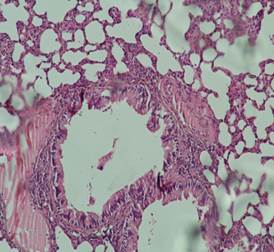

Гистологический срез биоптатов тканей бронхолегочной системы животных из контрольной группы показал отсутствие изменений в тканях стенки дыхательных путей. Не было выявлено гиперплазии эпителия, воспалительной инфильтрации в подслизистом слое, а также выраженного эмфизематозного расширения альвеол и фиброзных изменений в тканях (рис. 5).

Рис. 5. Гистологическое исследование образца ткани легкого животного контрольной группы (окраска гематоксилином и эозином; х100).

Источник: составлено авторами по результатам данного исследования